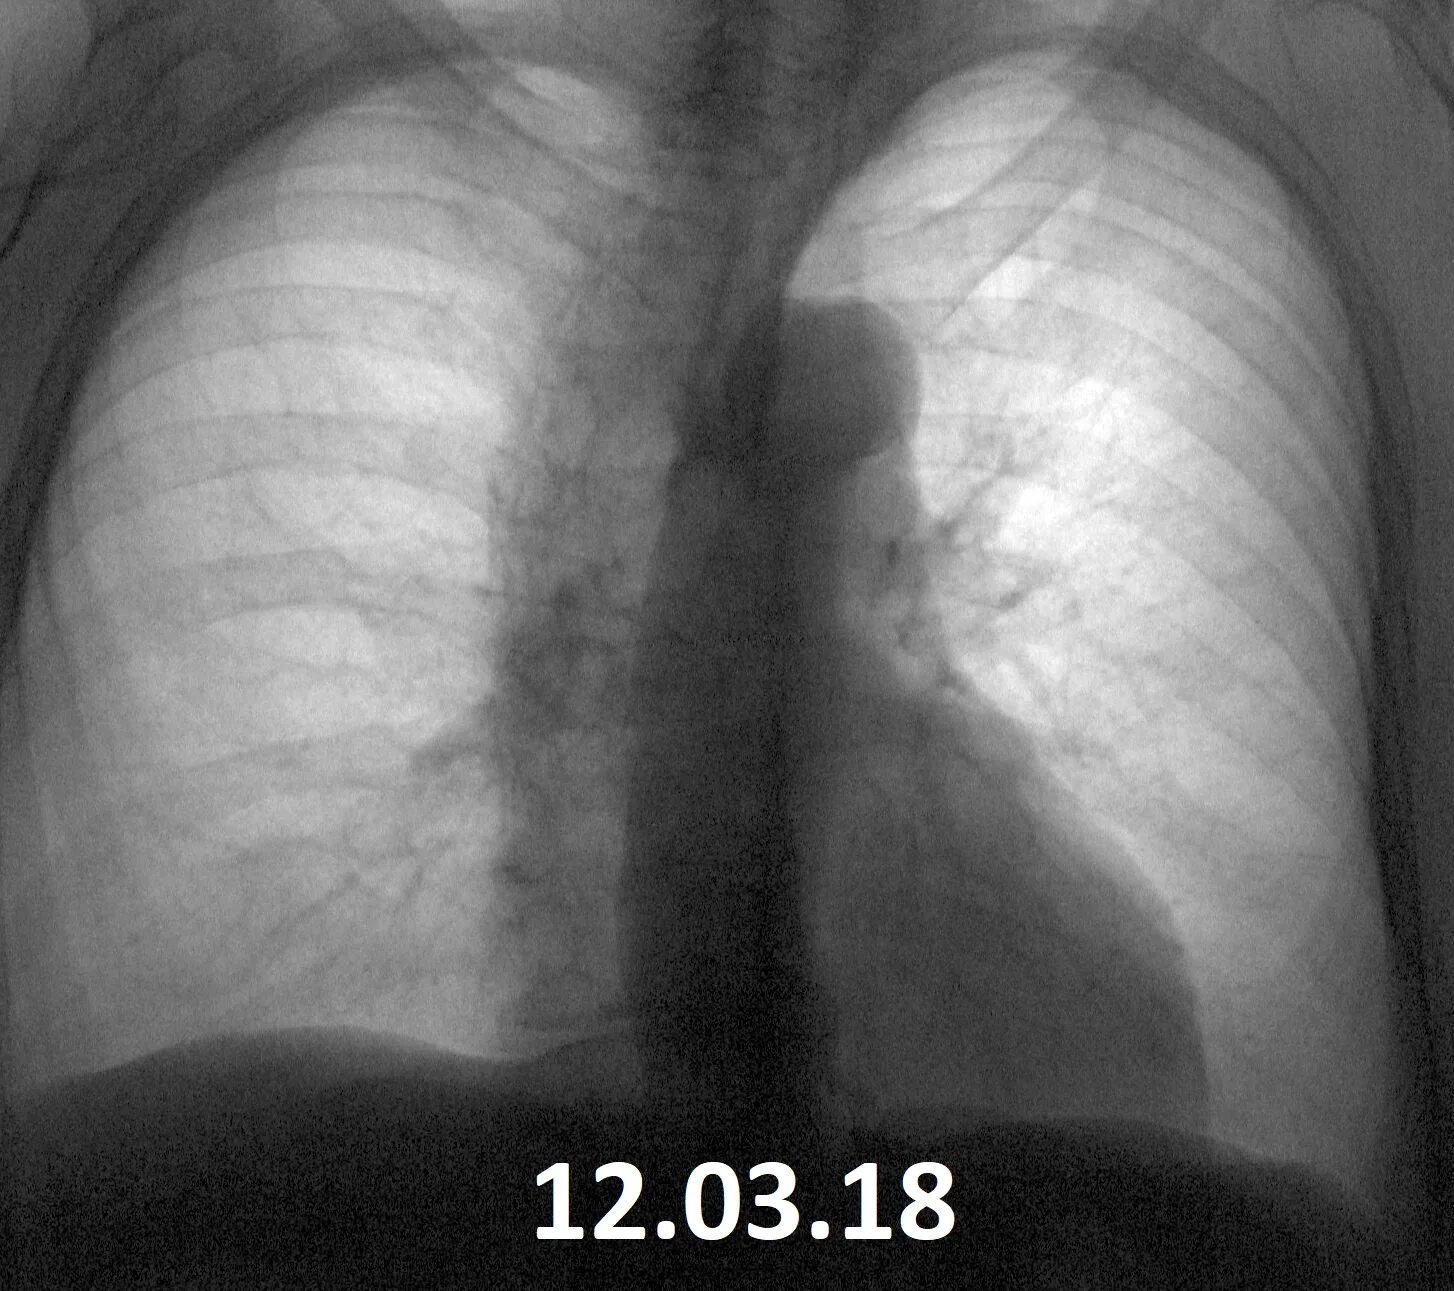

Сделала флюорографию будучи беременной